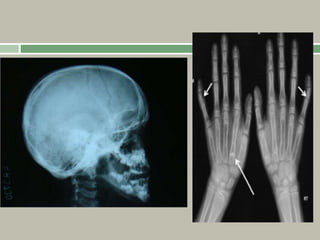

Radiographic features

Hypoplastic or absent clavicles,

Multiple wormian bones in the skull,

Widened symphysis pubis and sacroiliac joints,

Coxa vara,

Scoliosis and spondylolysis,

Hypoplastic/absent terminal phalanges,

Increased length of the second metacarpals.

Achondroplasia

Relative shortening of the middle finger gives the

appearance that all fingers are the same length

(‘starfish

hand’). An abnormally increased separation of the

middle and ring fingers gives the hand a ‘trident’

appearance.